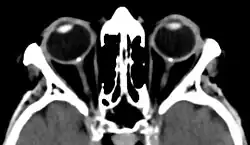

| Bilateral optic disc drusen in computed tomography seen as dense spots at the optical disc | |